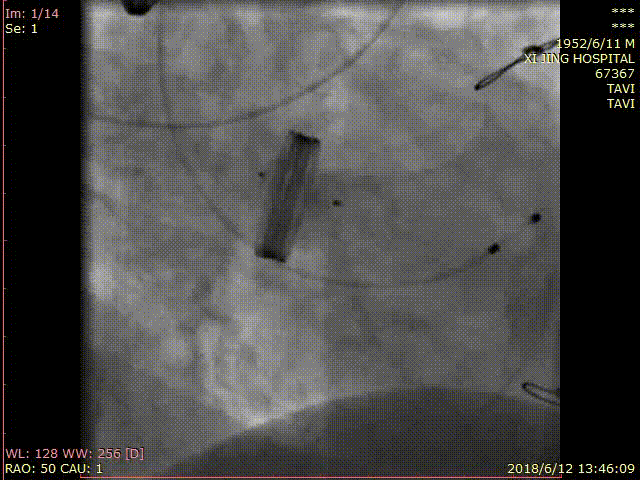

术前CT测量

瓣环:24.4mm;LVOT:22.7mm;

瓦氏窦:32.0*31.4*32.0mm;

升主动脉:32.6mm;左冠高度:17.3mm;

右冠高度:17.3mm;钙化积分:1.1mm³;

瓣环与水平面夹角:34°;

髂外动脉:6.4*8.0mm,6.8*7.9mm。

CT评估

主动脉瓣为三叶瓣,瓣叶肥厚且冗长,CT下可见少量钙化点,窦部结构和冠脉高度尚可,人工金属二尖瓣环,最高处距离主动脉瓣环6.9 mm。大血管走行自然,未见明显迂曲及钙化斑块,下肢血管内径可。